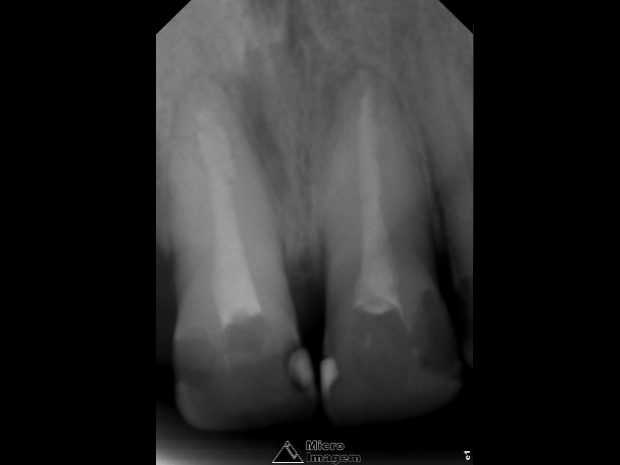

Paciente do gênero masculino, 32 anos, apresentou-se com quadro clínico de necrose pulpar dos elementos dentais 11 e 12 (figura 1), associado à presença de reabsorção interna, sendo submetido ao tratamento endodôntico em ambos os elementos.

- Figura 1